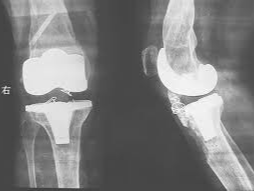

나이가 들면 관절 사이 연골이 점차 닳아 없어지면서 뼈와 뼈가 직접 맞닿아 통증을 유발합니다. 특히 무릎은 체중을 지탱하는 관절로써 손상되기 쉬우며, 다음과 같은 증상이 있다면 인공관절 수술이 필요할 수 있습니다.

이런 경우에는 무릎 인공관절 치환술이 가장 효과적인 치료법으로 여겨지며, 수술 후에는 통증 완화 및 활동 능력 회복이 가능합니다.

일반적으로 무릎 인공관절 치환술은 한쪽 무릎 기준 300만 원에서 500만 원까지 발생할 수 있습니다. 수술 전 검사비, 입원비, 인공관절 재료비, 수술 후 재활치료까지 포함하면 금액은 더 늘어날 수 있습니다.